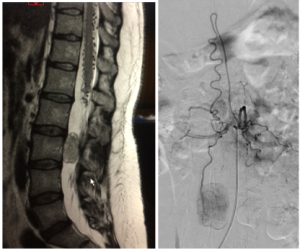

Prueba de elección para tumores de columna y médula espinal. Evalúa partes blandas, relación con la médula y raíces, y detecta compresión, edema, necrosis o hemorragia intratumoral.

Indicado cuando se sospecha metástasis vertebral, para localizar el tumor primario.

- Cirugía vertebral: Recomendable cuando:

- Se desconoce la naturaleza del tumor y se requiere biopsia.